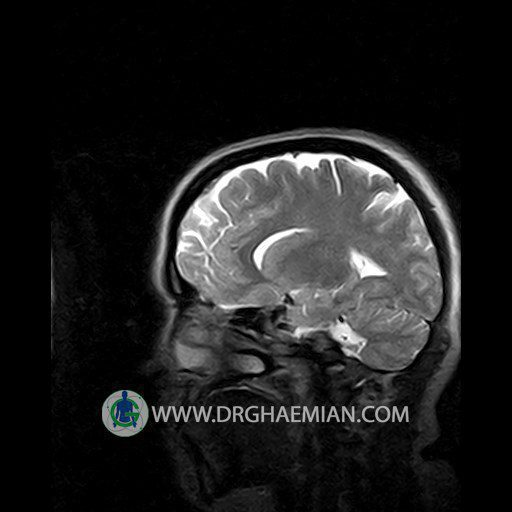

پزشکان اغلب از تصویربرداری ام آر آی برای تشخیص و درمان عارضه های پزشکی که فقط با استفاده از اشعه ایکس یا میدان مغناطیسی و امواج رادیویی قابل مشاهده است، استفاده می کنند. دستگاه ام آر آی تصاویر دقیق از ساختار های داخلی بدن ایجاد می کند. در این کیس نوریت اوربیت چب و سلای خالی بیمار مشاهده می شود.

Technique:Axial T1 , Axial , sagittal , coronal FSE T2 , coronal T1, sagittal fat sat T2 , Axial , sagittal T1 post Gd .

– Small fluid around the left optic nerve with mild edema suggestive for left optic neuritis

– Extension of suprasella cistern to sella with thin pituitary gland in floor of sella ( empty sella )

are seen